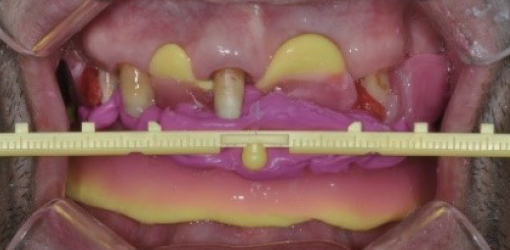

4. Place the VPS bite registration material to align the center of the POP stick with a pre-marked middle line on the patients front

5. Adjust the POP stick to be parallel to the patient’s interpupillary line

6. To create left-right symmetry of the maxillary arch, adjust the stick of the POP BOW with the left and right of the forehead to be symmetrical when viewed from above the patient’s head

7. After the VPS bite registration material has hardened, adjust the left and right POP arms to be parallel to Camper’s line marked in advance

4. Place the VPS bite registration material to align the center of the POP stick with a pre-marked middle line on the patients front

5. Adjust the POP stick to be parallel to the patient’s interpupillary line

6. To create left-right symmetry of the maxillary arch, adjust the stick of the POP BOW with the left and right of the forehead to be symmetrical when viewed from above the patient’s head

7. After the VPS bite registration material has hardened, adjust the left and right POP arms to be parallel to Camper’s line marked in advance